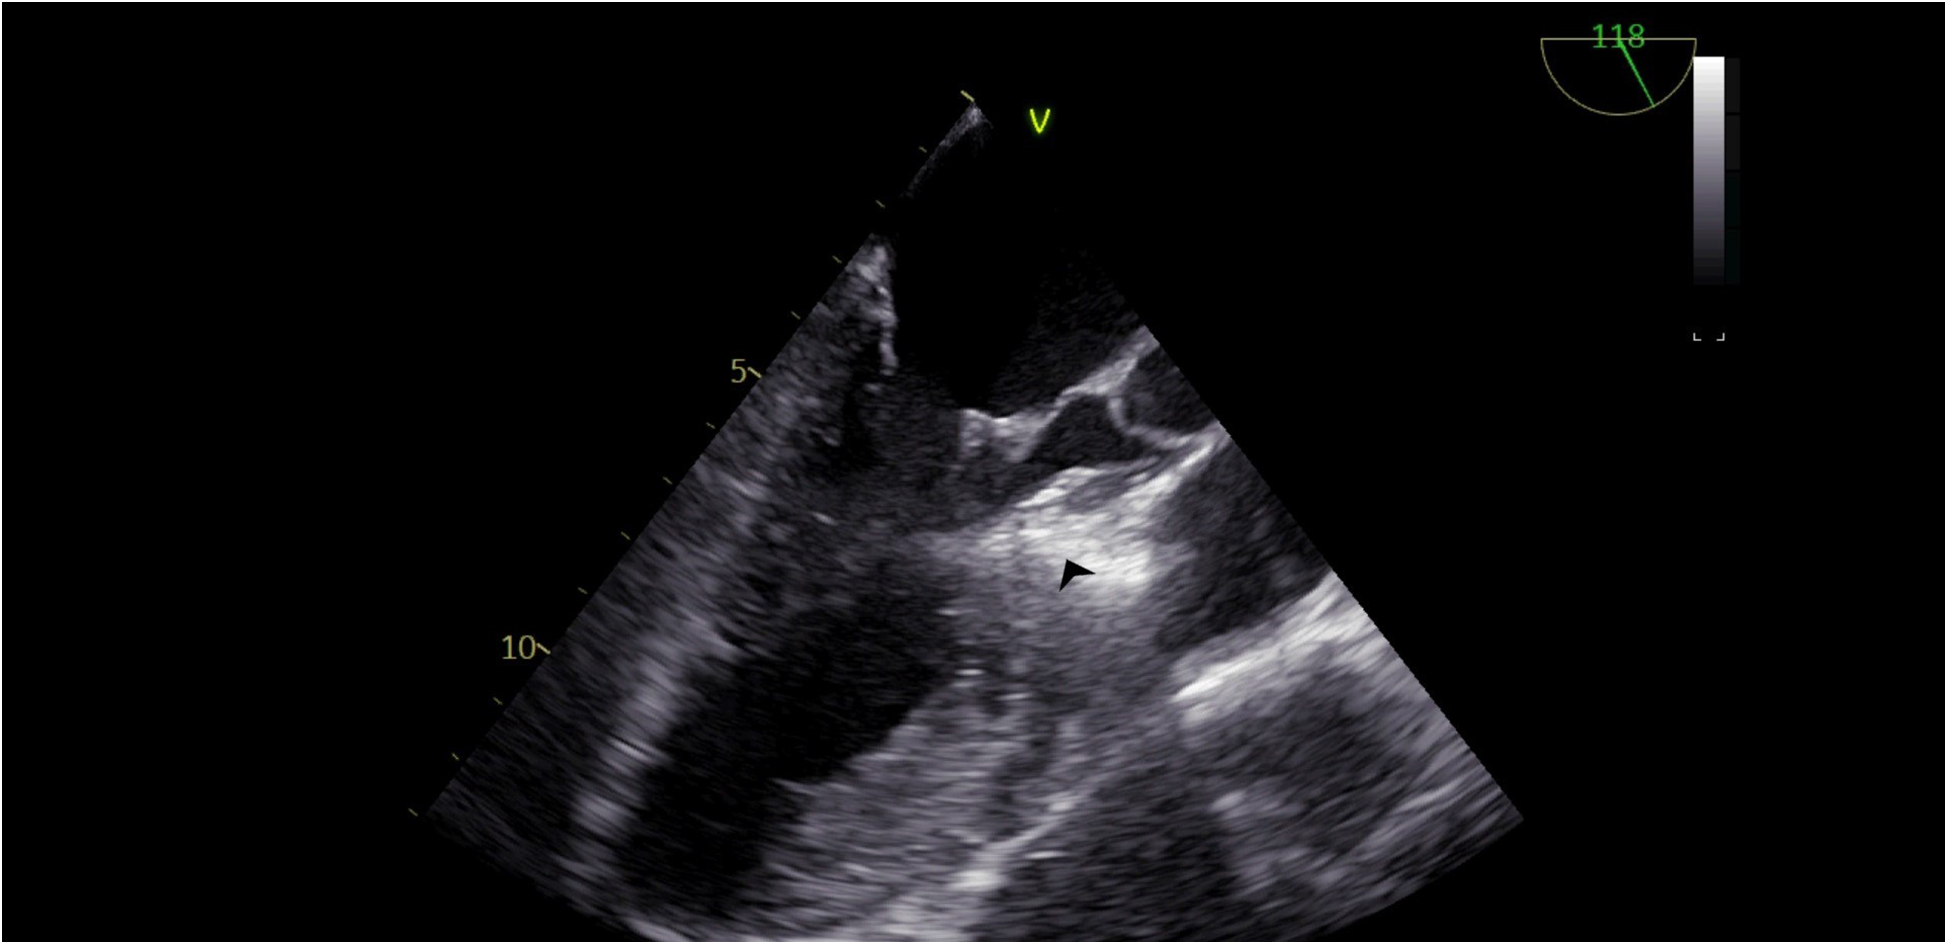

Figure 4

TEE view, following the injection of cocktail fluid through the central lumen of the over-the-balloon wire. Isolated brightness in the basal interventricular septum is clearly seen.

Our agitated contrast substance included cocktail fluid (agitated 5 mL of saline plus 0.5 mL blood of the patient, shaken in a three-way-stopcock (Figure 2). In TEE, the basal interventricular septum was compared with the same views recorded at baseline. Finally, we observed an enhancement of the basal septum (Figures 3, 4). Then, 1–2 mL of ethanol (absolute alcohol 96%–99%) was injected into the TSAB. We injected alcohol into the target perforatory artery in a step-by-step manner to observe a reduction in mitral regurgitation and QT prolongation at electrocardiographic monitorization (initially, 0.5 mL alcohol, then by increasing the dosage up to 3 mL). Two of the 14 patients had a single perforator artery with a double branch. In these patients, we performed superselective septal catheterization. Then, we administered contrast agents to both branches. Next, we found the correct branch feeding basal interventricular septum.

We clearly observed the related target area in TEE. We cared about the absence of the contrast in other myocardial areas for the safety of the technique in this procedure.